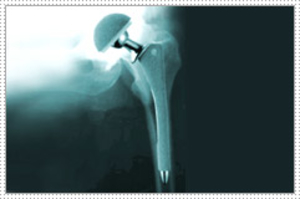

What is total joint replacement?Also called arthroplasty, total joint replacement is a surgical procedure in which both sides of a joint are remove...

What is a hip replacement? How does a total hip replacement eliminate pain? What part of the hip is replaced? Which to choose? An uncemented or a c...